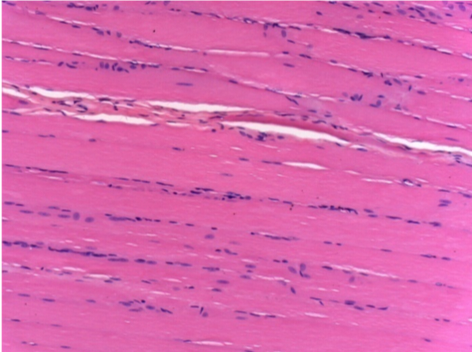

Через 3 місяці (90 днів) після ін'єкції Ендопіл 0,1 мл в правий претибіальний м'яз.

7 місяців (210 днів) після ін'єкції 0,1 мл Ендопіл в правий претибіальний м'яз.

Повна Restitutio ad integrum через 7 місяців

Л :Контроль 50x210 днів

П:50X-210 днів